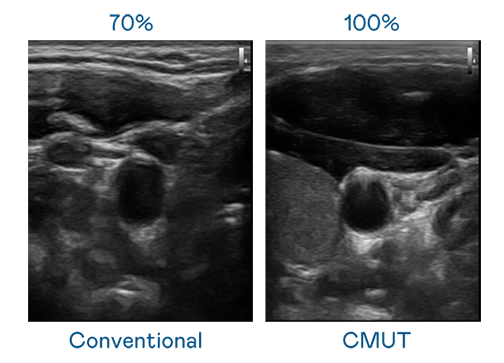

CMUT 技术是一种用电容式微机电元件来产生超音波讯号的技术。与传统 PZT 压电式技术相比,CMUT 频宽增加 30%,更宽频的超音波讯号让影像解析度大幅提升,是实现高影像品质医疗超音波扫描、促进精准医疗发展的关键技术。

大频宽带来超清晰影像

超音波影像的解析度高低,首先取决于探头能发出的讯号频宽。918博天堂 CMUT 可提供高清晰的超音波讯号,提供高频宽、高灵敏度、影像纹理细节更高的超音波影像,协助医护人员缩短影像判读时间及利用精准的医疗影像进行诊断。